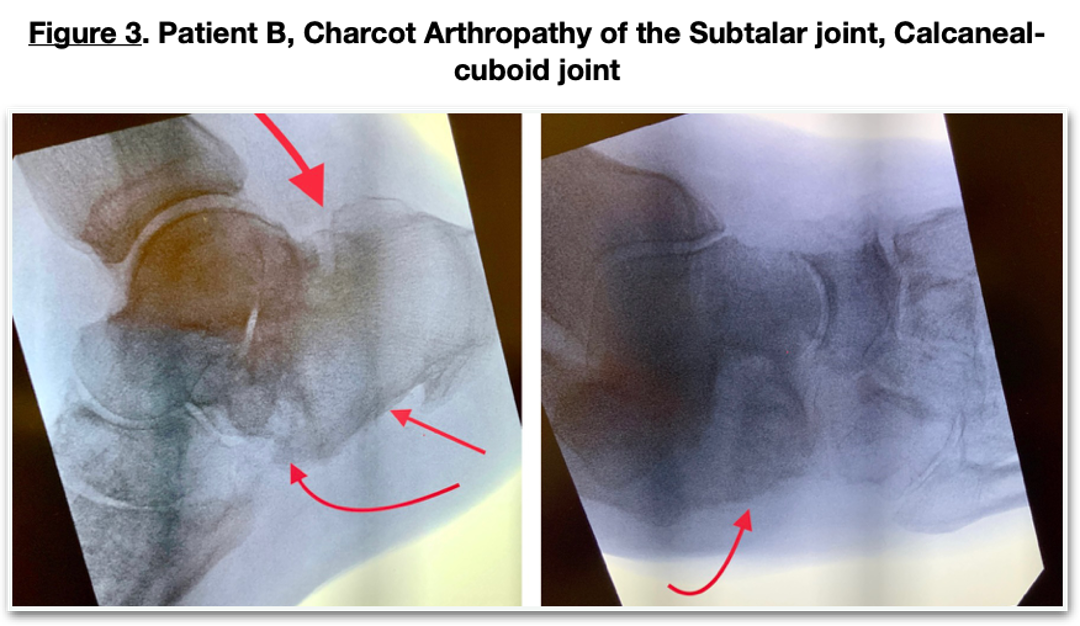

The patient presented to the office with a swollen, painful left midtarsal joint. X-rays (Figure 6) revealed numerous subchondral cysts with osteolysis at the lateral midtarsal joint consistent with an acute Charcot neuroarthropathy. CT confirmed the Charcot arthropathy showing multiple subchondral cysts (Figure 7) and subchondral edema. He was immobilized with a diabetic CAM boot. Follow-up X-rays revealed an increase in osteolysis and a slight lateral shift of the lateral column, indicating a progression of the acute neuroarthropathic process. He chose to have percutaneous placental tissue injections into the acute areas of the midfoot. This procedure was done under fluoroscopic guidance with placental cells injected into the metatarsal bases at the cystic and intercuneiform regions. He was immobilized with the CAM boot, and this area progressed uneventfully to a stable but arthritic construct. (Figure 8) The acute inflammatory component of the Charcot subsided within days of the injection.